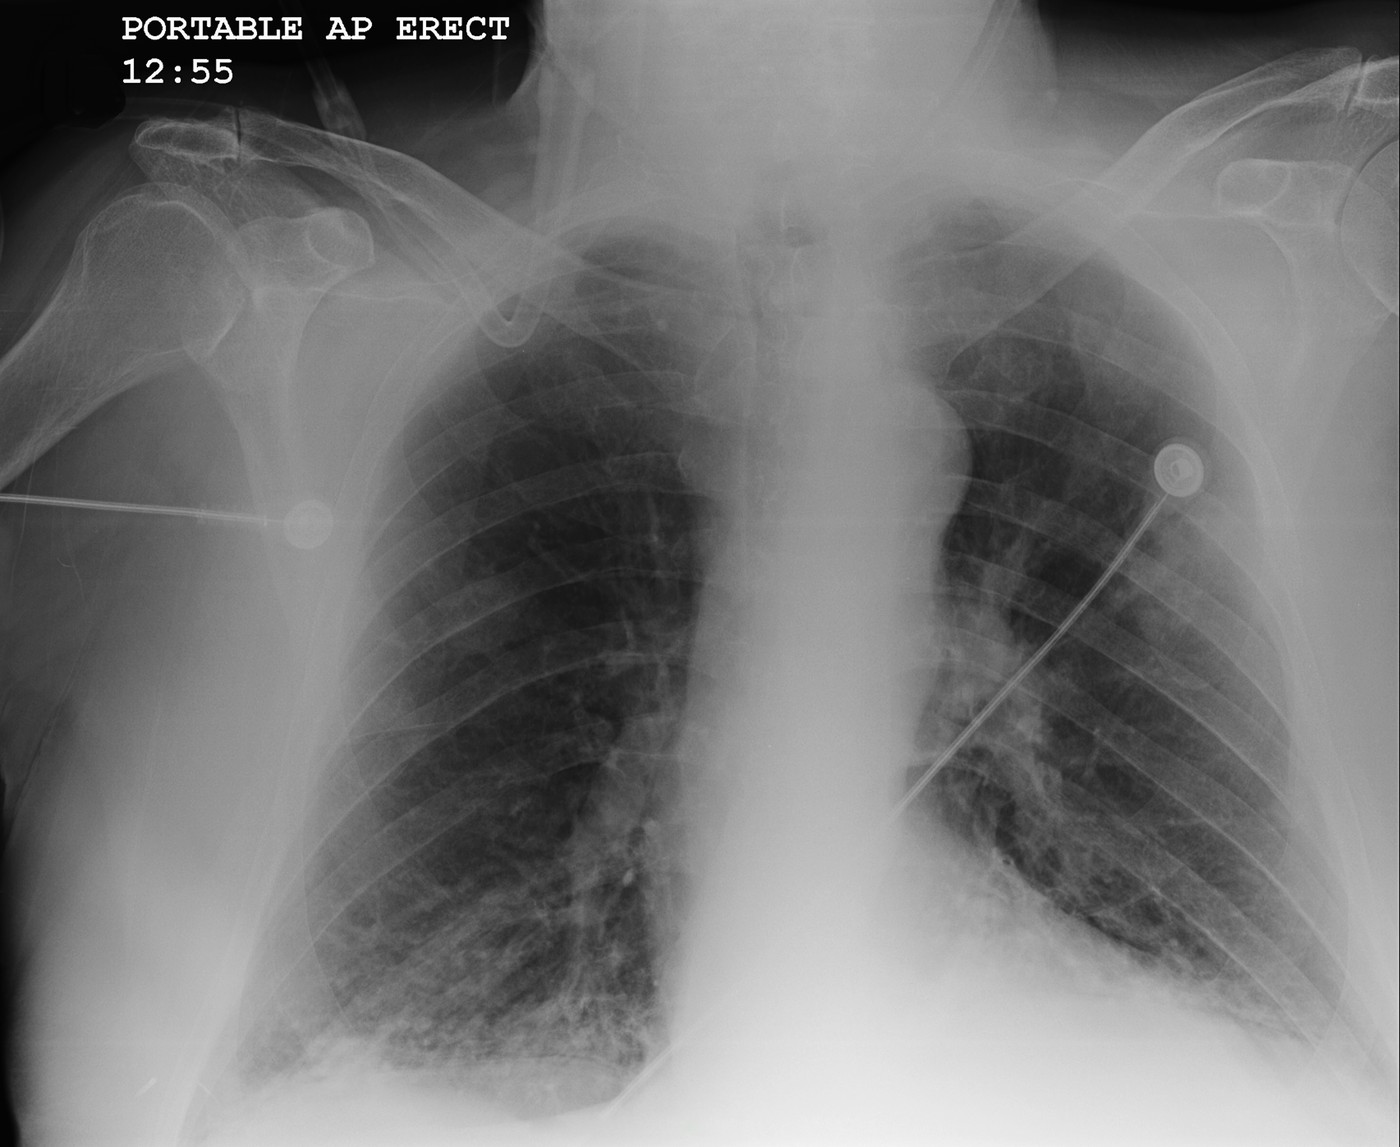

Hronična opstruktivna bolest pluća Foto: Callista Images / ImageSource / Profimedia Hronična opstruktivna bolest pluća Foto: Callista Images / ImageSource / Profimedia Hronična opstruktivna bolest pluća Foto: Callista Images / ImageSource / Profimedia Bolest sa kojom se borio Bora Čorba je hronična i sve veći broj ljudi u Srbiji pati od nje: Ovo su simptomi i evo koga najviše pogađa autor: Milorad Milovanović Zdravlje 04. sep. 2024. 09:07 2 Podeli vest: Bora Đorđević, legendarni roker i frontmen grupe "Riblja čorba" preminuo je u bolnici u Ljubljani posle teške bolesti, potvrdili su iz "Riblje čorbe". Podeli vest: Oglas Bora Đorđević umro je u 72. godini posle komplikacija izazvane hroničnom opstruktivnom bolesti pluća - HOBP. Institut za plućne bolesti Vojvodine dao je smernice u slučaju lečenja ove bolesti i koji su simptomi. Šta je hronična opstruktivna bolest pluća? Hronična opstruktivna bolest pluća (HOBP) karakteriše se ograničenjem (smanjenjem) protoka vazduha u disajnim putevima. Ograničenje protoka vazduha je progresivno i udruženo sa zapaljenjskom reakcijom pluća na štetne čestice ili gasove. Reč hronična znači da se bolest ne povlači, opstruktivna – da je delimično blokiran protok vazduha u disajnim putevima, reč bolest – oboljenje, a pluća – da se dešava u plućima.Kod bolesnika sa HOBP manji su otvori disajnih puteva. U njih ulazi manje vazduha zato što su zidovi disajnih puteva zadebljali i otečeni, disajni putevi su stisnuti pod uticajem malih mišića koji ih okružuju i u njima se stvara sluz koju bolesnik iskašljava. Od HOBP najčešće obolevaju pušači ili bivši pušači, osobe koje žive u kućama sa mnogo gasova (sagorevanje u pećima za zagrevanje prostorija) ili one koje su radile na mestima gde je bilo puno prašine i dima. Većina bolesnika sa HOBP ima preko 40 godina, ali mogu oboleti i mlađi ljudi. Karakteriše se perzistentnim simptomima i ograničenjem protoka vazduha usled oštećenja u disajnim putevima i/ili plućnim alveolama nastalim zbog izloženosti (udisanja) štetnim česticama I gasovima Foto: Anna Maloverjan / Panthermedia / Profimedia | Karakteriše se perzistentnim simptomima i ograničenjem protoka vazduha usled oštećenja u disajnim putevima i/ili plućnim alveolama nastalim zbog izloženosti (udisanja) štetnim česticama I gasovima Foto: Anna Maloverjan / Panthermedia / Profimedia Osobe koje boluju od HOBP žale se na kašalj i iskašljavanje sluzavog ili "prljavog" ispljuvka, otežano dišu, guše se, ostaju bez daha prilikom fizičkog napora i potrebno im je duže vreme da se oporave nakon prehlade. Sa napredovanjem bolesti, tegobe postaju sve izraženije. Većina pacijenata kasno se javlja lekaru i smatra da je kašalj normalna pojava zbog pušenja.Kada se jave lekaru koji dijagnostikuje pravu prirodu bolesti, pacijenti dobijaju savet o daljem lečenju: prestanak pušenja (najvažniji i najbolji način da pomognete svojim plućima);izbegavanje mesta gde se puši, dima i mirisa koji vam smetaju;provetravanje prostorija u stanu;redovno uzimanje lekova iredovne vežbe disanja. Lečenje HOBP-a Za lečenje HOBP koriste se lekovi koji otklanjaju simptome širenjem disajnih puteva, smirivanjem upale i infekcije, a po potrebi i drugi za jačanje snage srčanog mišića. Za lečenje HOBP koriste se dozni aerosoli, tzv. pumpice pomoću kojih se lek unosi udisanjem (inhalacionim putem). To je najbolji, najkorisniji i najmanje štetan vid terapije jer lek deluje direktno na oboleli organ, unosi se mala doza, brzo se otklanjaju simptomi i nema neželjenih efekata. Treba naglasiti kako je pogrešno mišljenje da su pumpice štetne jer navodno stvaraju naviku i imaju negativan efekat. U toku epidemija gripa i respiratornih infekcija bolesnicima se preporučuje vakcinacija. U uznapredovalom stadijumu oboljenja, kada je kiseonik u krvi znatno niži, bolesnicima koji ispunjavaju uslove propisuje se dugotrajna oksigenoterapija u kućnim uslovima (DOT). Ona podrazumeva upotrebu kiseonika preko aparata koji se zove koncentrator kiseonika u kućnim uslovima. Tako je pacijent na stalnoj oksigenoterapiji (najmanje 16 sati u toku dana), i manje su potrebe za bolničkim lečenjem. HOBP je bolest od koje svake godine oboleva sve više ljudi i predstavlja veliki zdravstveni i socio-ekonomski problem pa je prevencija u smislu prestanka pušenja najbolji način za smanjenje učestalosti tog oboljenja. Namirnica koja je jača od antibiotika: Najbolje leči kašalj Fitnes i ishrana 0 Hronična bolest pluća od koje pati pola miliona Srba Zdravlje 0 bora čorba hronična opstruktivna bolest pluća Pratite nas na društvenim mrežama: Koje je tvoje mišljenje o ovoj temi? Učestvuj u diskusiji ili pročitaj komentare Budite prvi koji će ostaviti komentar Pošalji komentar Pročitaj komentare (2)